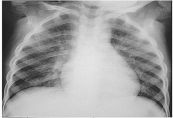

Viêm phổi là một bệnh nhiễm trùng phổi do vi khuẩn, virus, nấm, hoặc ký sinh trùng gây nên. Bài viết này sẽ tìm hiểu rõ hơn về viêm phổi điển hình. Mời các bạn tham khảo!